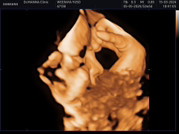

อัลตร้าซาวด์4มิติ

อยากถามแม่ๆว่าควรอัลตร้าซาวด์4มิติตอนกี่weeksดีคะพอดีอยากซาวด์ไว้ให้ลูกดูตอนแกโตแล้วมีแม่ๆๆคนไหนไปซาวด์แล้วบ้างคะ

คุณหมอแนะนำ 28 w ค่ะ

28-32 week ค่ะจะชัดมากๆ

28-32ค่ะ กำลังพอดี

หมอแนะนำ 28 week ค่ะ